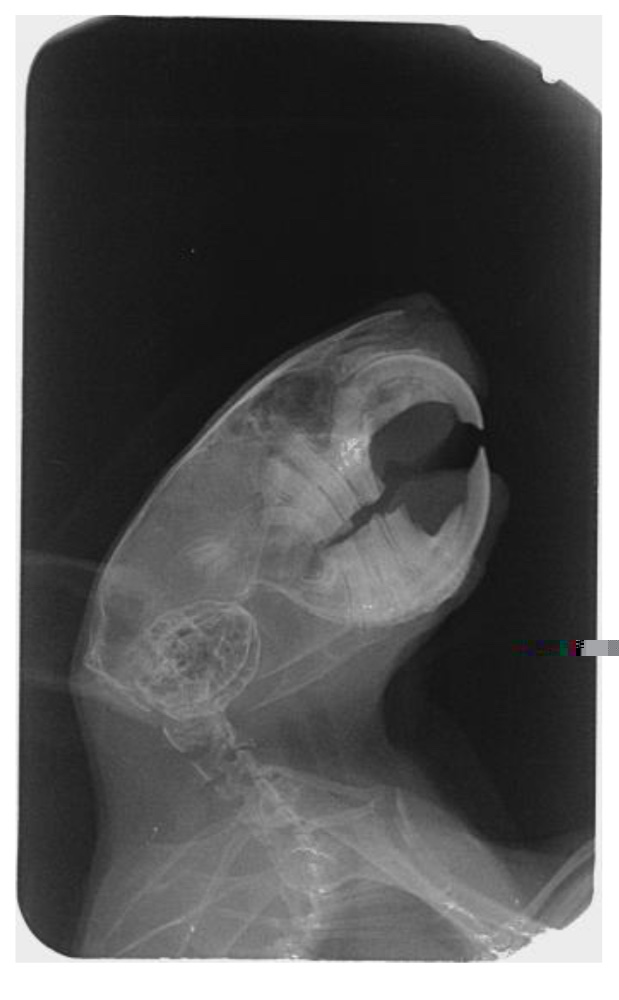

Hallo, Santiago wurde inzwischen unter einer Gasnarkose geröntgt- und hat es überlebt. *nicken* Die Tierärztin meinte, dass er ein Odontom (wuchernde Zahnwurzel?) hat, aber dies noch nicht so schlimm sei, dass man die OP riskieren würde. (Da müsste man von außen an den Kiefer ran)

Ich hänge mal die Röntgenbilder an- leider erkenne ich dort garnichts. Kann einer von euch etwas dazu sagen, wie schlimm es ist?

3272C9C6-C060-4FCD-AA24-A25F13AB765A.jpeg

3272C9C6-C060-4FCD-AA24-A25F13AB765A.jpeg (85.08 KiB) 2172 mal betrachtet